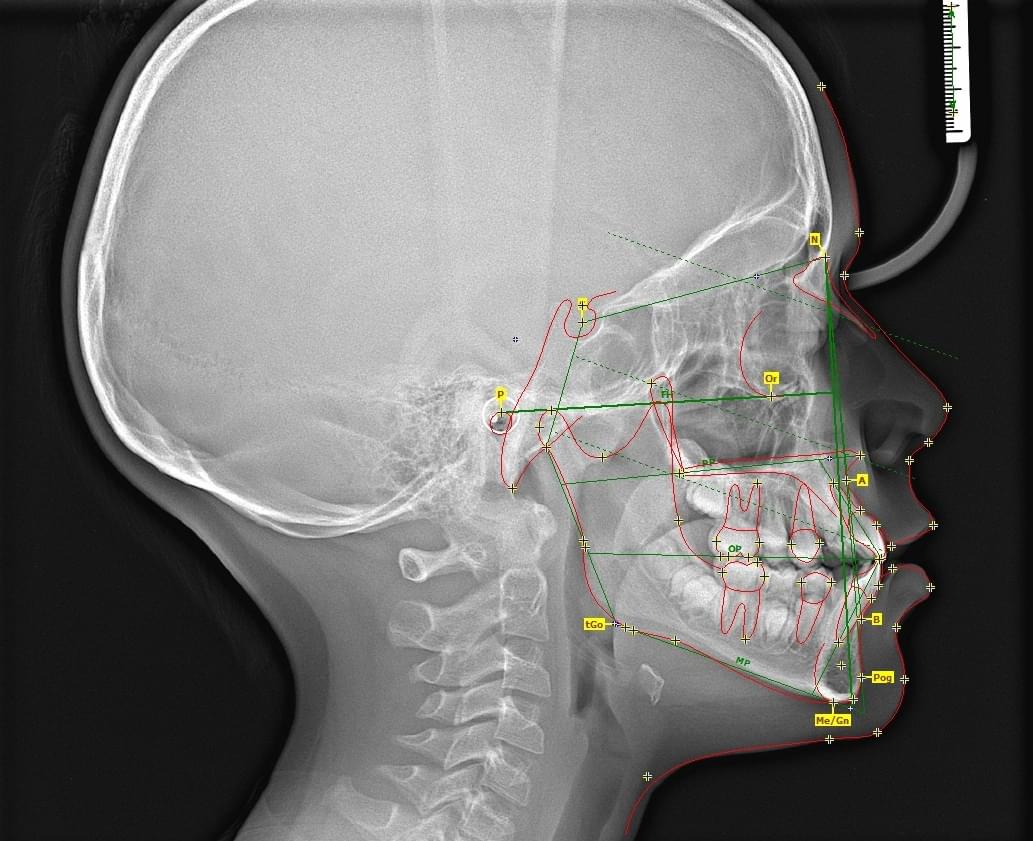

1️⃣ ТРГ у боковій проекції (Профіль)

● Це «золотий стандарт» перед початком ортодонтичного лікування.

● Що показує: Вигляд черепа збоку. Дозволяє оцінити профіль обличчя, нахил різців, як верхня

щелепа співвідноситься з нижньою.

● Для чого: Щоб спланувати виправлення прикусу (наприклад, якщо нижня щелепа висунута вперед або

занадто засунута назад).

✍ Розрахунок ТРГ:

Це окрема діагностична послуга, під час якої лікар-діагност оцифровує знімок, розставляє анатомічні точки та вимірює кути і відстані між кістками черепа та зубами. Вартість послуги тут